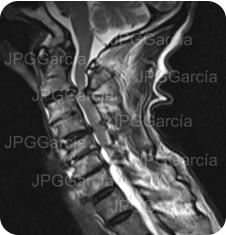

Tratamiento de hernia de disco cervical alta con compromiso medular

Estudio de control postquirúrgico inmediato